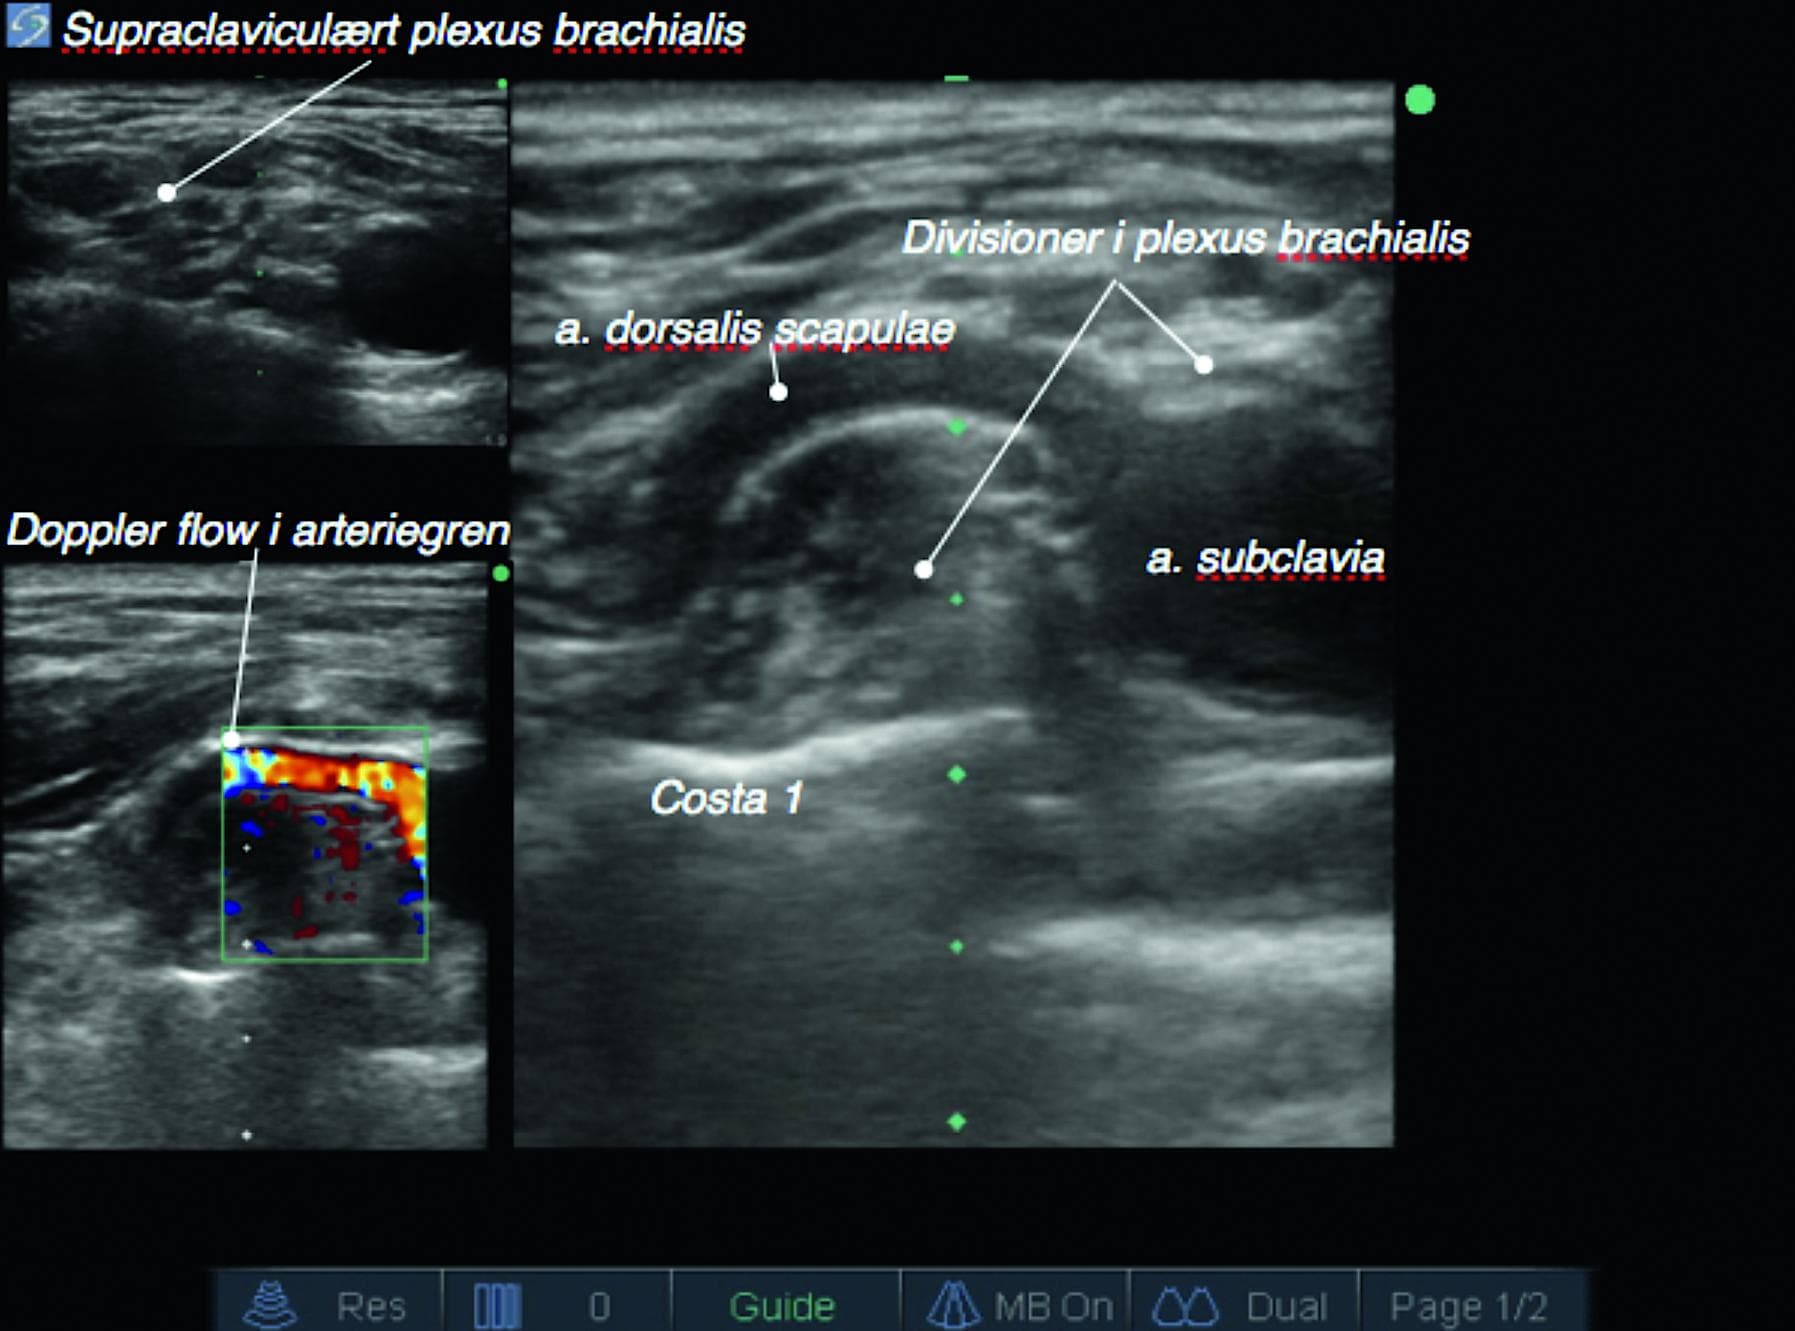

Hos mennesket er der ofte en anatomisk standard med en række varianter. I plexus brachialis er der beskrevet talrige varianter. På billedet ses plexus brachialis med en stor arteriel sidegren fra arterie subclavia, arteria dorsalis scapulae. Billedet understreger vigtigheden af at visualisere injektionsområdet for at reducere risikoen for intravasal injektion. Variationen med en stor sidegren fra arterie subclavia, som går igennem pleuxus brachialis, er i litteraturen beskrevet som værende normal [1].